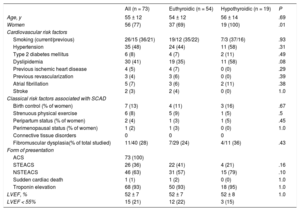

RESULTSThe study included 73 consecutive patients with SCAD; 26% of them were classified as having hypothyroidism. Most patients with SCAD were women (77%; n = 56), Caucasian, and with relatively few cardiovascular risk factors. The differences in the baseline characteristics of patients with SCAD according to their thyroid status are shown in Table 1. Most patients with SCAD and hypothyroidism received thyroid hormone replacement therapy (74%, n = 14) and maintained good metabolic control (86%, n = 12). Antithyroid antibodies were elevated in 16% (n = 3). All hypothyroid patients with SCAD were female (100% vs 69%; P = .01), with a nonsignificant tendency for higher prevalences of FMD (36% [4/11] vs 24% [7/29]; P = .43) and dyslipidemia (58% [n = 11] vs 35% [n = 24]; P = .09) vs euthyroid patients. In all patients, the form of presentation was ACS (Table 1). The angiographic characteristics of the 2 groups are compared in Table 2. Most patients had a single long (> 25mm) type 1 or 2 dissection located in the anterior descending artery and in distal coronary segments. SCAD patients with hypothyroidism had a higher frequency of distal vessel involvement (74% [n = 14] vs 41% [n = 22]; P = .03) and tended to show a more diffuse involvement (84% [n = 16] vs 63% [n = 34]; P = .1). Via quantitative coronary angiography measurement, the vessels of patients with SCAD tended to be smaller (mean proximal reference diameter on quantitative coronary angiography, 2.7 ± 0.7mm vs 3.1 ± 0.7mm; P = .13) and with more diffuse involvement (length on quantitative coronary angiography, 44 ± 27mm vs 37 ± 37mm; P = .059).

Clinical and Demographic Characteristics of the Spontaneous Coronary Artery Dissection Group

| All (n = 73) | Euthyroidic (n = 54) | Hypothyroidic (n = 19) | P | |

|---|---|---|---|---|

| Age, y | 55 ± 12 | 54 ± 12 | 56 ± 14 | .69 |

| Women | 56 (77) | 37 (69) | 19 (100) | .01 |

| Cardiovascular risk factors | ||||

| Smoking (current/previous) | 26/15 (36/21) | 19/12 (35/22) | 7/3 (37/16) | .93 |

| Hypertension | 35 (48) | 24 (44) | 11 (58) | .31 |

| Type 2 diabetes mellitus | 6 (8) | 4 (7) | 2 (11) | .49 |

| Dyslipidemia | 30 (41) | 19 (35) | 11 (58) | .08 |

| Previous ischemic heart disease | 4 (5) | 4 (7) | 0 (0) | .29 |

| Previous revascularization | 3 (4) | 3 (6) | 0 (0) | .39 |

| Atrial fibrillation | 5 (7) | 3 (6) | 2 (11) | .38 |

| Stroke | 2 (3) | 2 (4) | 0 (0) | 1.0 |

| Classical risk factors associated with SCAD | ||||

| Birth control (% of women) | 7 (13) | 4 (11) | 3 (16) | .67 |

| Strenuous physical exercise | 6 (8) | 5 (9) | 1 (5) | .5 |

| Peripartum status (% of women) | 2 (4) | 1 (3) | 1 (5) | .45 |

| Perimenopausal status (% of women) | 1 (2) | 1 (3) | 0 (0) | 1.0 |

| Connective tissue disorders | 0 | 0 | 0 | |

| Fibromuscular dysplasia(% of total studied) | 11/40 (28) | 7/29 (24) | 4/11 (36) | .43 |

| Form of presentation | ||||

| ACS | 73 (100) | |||

| STEACS | 26 (36) | 22 (41) | 4 (21) | .16 |

| NSTEACS | 46 (63) | 31 (57) | 15 (79) | .10 |

| Sudden cardiac death | 1 (1) | 1 (2) | 0 (0) | 1.0 |

| Troponin elevation | 68 (93) | 50 (93) | 18 (95) | 1.0 |

| LVEF, % | 52 ± 7 | 52 ± 7 | 52 ± 8 | 1.0 |

| LVEF < 55% | 15 (21) | 12 (22) | 3 (15) | |

ACS, acute coronary syndrome; LVEF, left ventricular ejection fraction; NSTEACS, non-ST-segment elevation acute coronary syndrome; SCAD, spontaneous coronary artery dissection; STEACS, ST-segment elevation acute coronary syndrome.

Unless otherwise indicated, the data represent No. (%) or mean ± standard deviation.